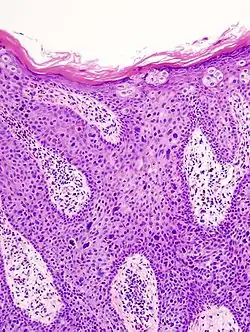

Characteristics

Histopathologically, the epidermis in SCC in situ (Bowen’s disease) will show hyperkeratosis and parakeratosis. There will also be marked acanthosis with elongation and thickening of the rete ridges. These changes will overly keratinocytic cells which are often highly atypical and may in fact have a more unusual appearance than invasive SCC. The atypia spans the full thickness of the epidermis, with the keratinocytes demonstrating intense mitotic activity, pleomorphism, and greatly enlarged nuclei. They will also show a loss of maturity and polarity, giving the epidermis a disordered or “windblown” appearance.

Two types of multinucleated cells may be seen: the first will present as a multinucleated giant cell, and the second will appear as a dyskeratotic cell engulfed in the cytoplasm of a keratinocyte. Occasionally, cells of the upper epidermis will undergo vacuolization, demonstrating an abundant and strongly eosinophilic cytoplasm. There may be a mild to moderate lymphohistiocytic infiltrate detected in the upper dermis.[33]